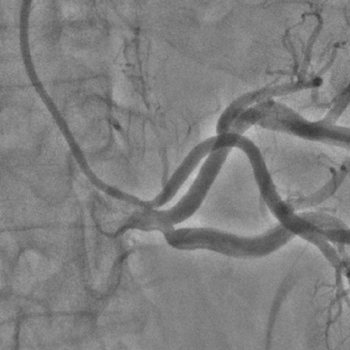

Бифуркационное стентирование почечной артерии

Ангиографическое исследование аорты и селективная ангиография сосудов почек выявило критический стеноз a. segmenti inferioris и короткую a. renalis sinistra